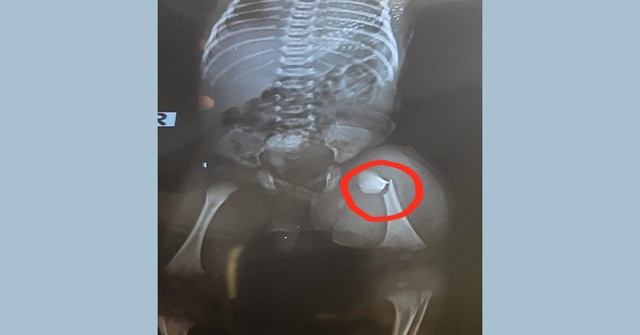

নবজাতকের পা ভাঙ্গার অভিযোগ চিকিৎসকের বিরুদ্ধে